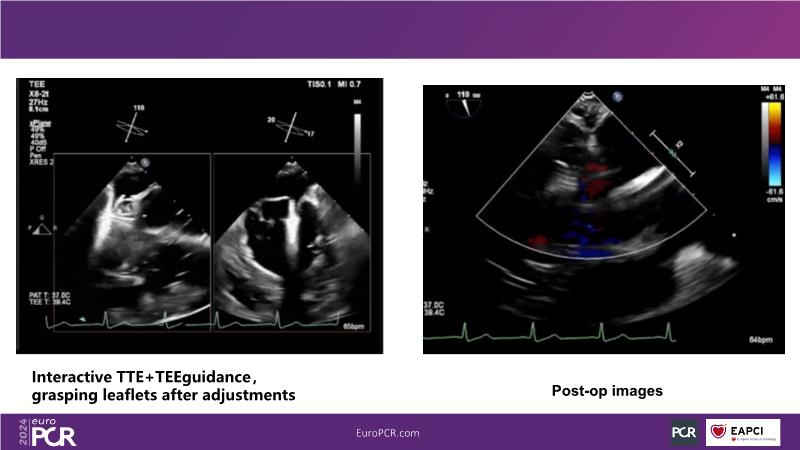

Watch this session to gain insights into the clinical evidence of mitral TEER therapy for the Asian population, learn techniques for implanting a MitraClip in patients with challenging anatomy, and understand how to use the four clip sizes for optimal outcomes. The session also covers educational aspects of clipping in dextrocardia, the benefits of reserve bending of the transseptal needle for tenting and puncture, new steering maneuvers for dextrocardia patients, and the importance of understanding anatomy and collaborating closely with the echo team for success.